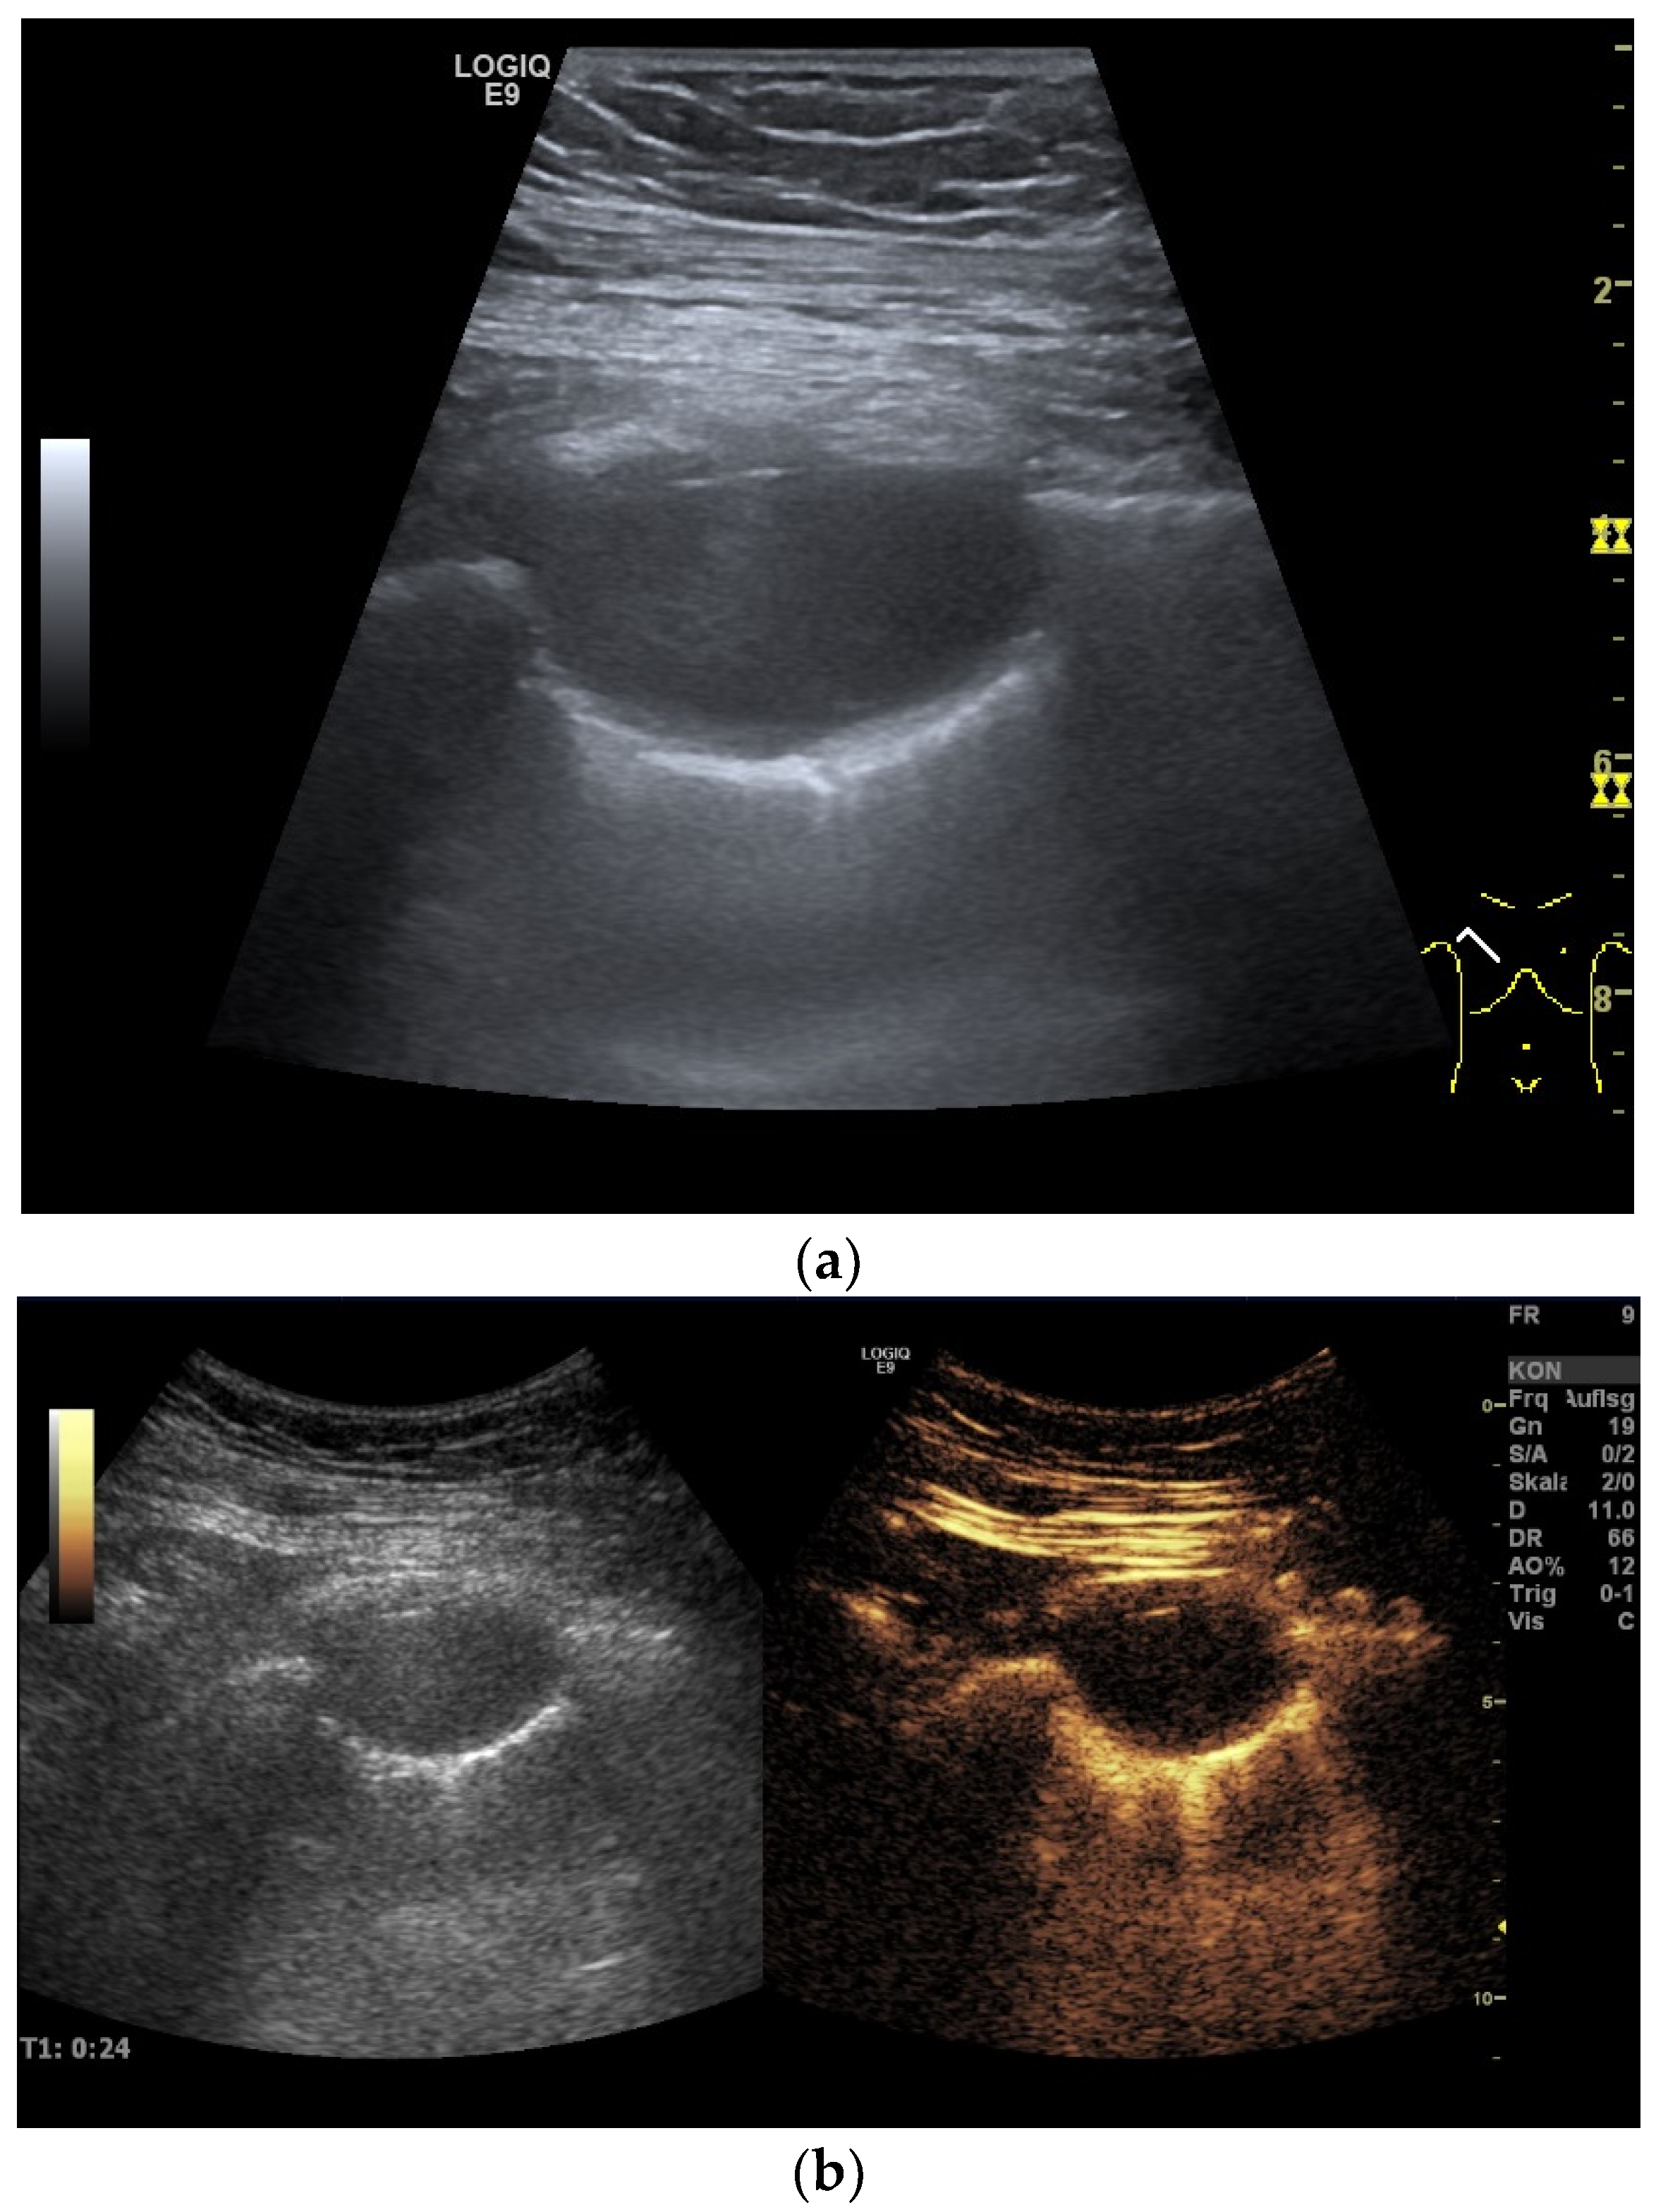

| Splenosis | Round, homogeneous lesions. Macrovessels on CDI are possible. Spleen-typical contrast behavior in CEUS with long-lasting contrast enhancement over several minutes. |